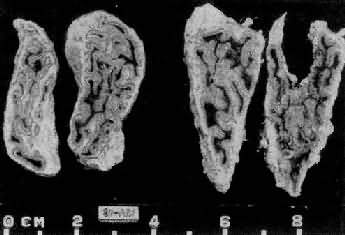

1.垂体性Cushing综合征 主要由垂体ACTH细胞腺所引起,少数由于下丘脑异常分泌过多的促皮质释放因子(CRF)所致。血清中ACTH增高,双侧肾上腺呈弥漫性中度肥大,重量可达20g(正常8g左右),切面皮质厚度可超过2mm,呈脑回状。镜下主要是网状带及束状带细胞增生(图15-13、图15-14)。

图15-13 肾上腺皮质弥漫增生(大体)

肾上腺肥大,皮质弥漫性增厚,切面呈脑回状